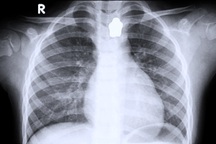

Lo sợ mắc các bệnh đường hô hấp như viêm phổi, anh T. đi khám ở bệnh viện địa phương và được chỉ định chụp X-quang phổi nhưng không thấy bất thường.